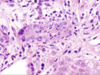

What is the appearance of the macrophages in this histology of someone suffering from chronic biliary obstruction?

• What gives them this appearance?

Macrophages = Foamy from Retained Bile Salts